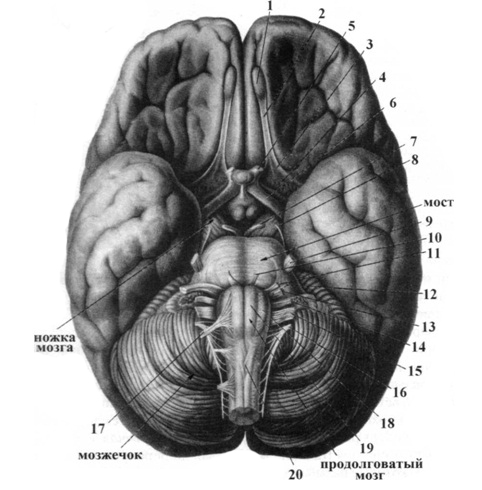

Необычные объекты: Переднее продырявленное вещество

Раздел: Альбом открытий